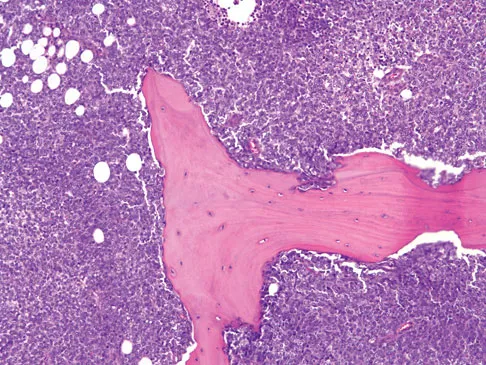

A healthy 16-year-old boy has had increasing pain in the right knee for the past 3 months. Examination reveals warmth and swelling around the distal femur. Radiographs and an MRI scan are shown in Figures 51a through 51c, and a biopsy specimen is shown in Figure 51d. What is the most likely diagnosis?

The radiographs show a bone-producing lesion in the distal femoral metaphysis in this case of classic osteosarcoma presenting in the most common location, the distal femur. The coronal MRI scan reveals a marrow-occupying lesion with extension into the soft tissues. The histology shows osteoid production by pleomorphic cells consistent with an osteosarcoma. Ewing's sarcoma is a bone tumor characterized by uniform small blue cells on histology. Rhabdomyosarcoma is the most common childhood soft-tissue sarcoma. Osteomyelitis has an inflammatory appearance on histology. Malignant fibrous histiocytoma of bone has a lytic radiographic appearance and a pleomorphic storiform pattern without osteoid on histology. Wold LE, Adler CP, Sim FH, et al: Atlas of Orthopedic Pathology, ed 2. Philadelphia, PA, WB Saunders, 2003, p 179.